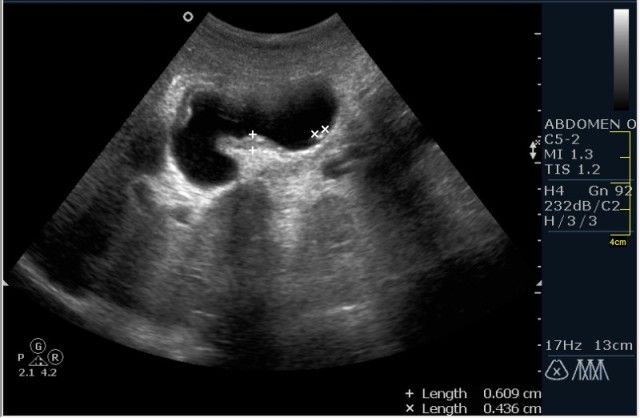

Мужчина 42 года; жалобы на периодические боли в эпигастрии. УЗИ области жёлчного пузыря выявило интересную картину; наблюдается фокальное утолщение стенок пузыря в области тела. Интересно узнать Ваше мнение?

В Желчном пузыре определялся мелкий конкремент и диффузное равномерное гипоэхогенное утолщение стенки на отграниченном участке, заключение морфологов-воспaлительный процесс (признаки холецистита).

Мне интерено, а почему Вы решили что это аденомиоматоз? На представленных сонограммах нет признаков этого заболевания, за исключением фокального утолщения стенки (что крайне не специфично, см. ниже). Если мы не находим пристеночных синусов (Ашоф -Ракитанского) образующихся за счёт неравномерной гиперплазии эпителия ЖП с протрузией эпителия в стенку, и не видим гиперэхогенные фокусы в стенке за счёт кристаллов холестерола; мы не можем выставлять диагноз аденомиоматоз. В нашем случае мы имеем дело с равномерным гипоэхогенным утолщением (см. сонограммы призведённые линейным датчиком с высоким разрешением).